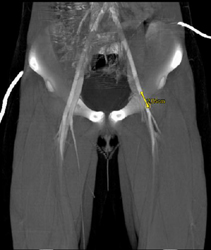

Clot in Superficial Femoral Artery (SFA) Due to Trauma in A Child-MIP Vs VRT